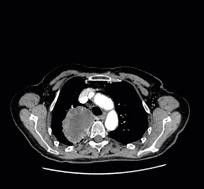

Longfoto en CT-scan van een 62-jarige patiënte die rookt en sinds enkele weken bloed ophoest. Ter hoogte van de bovenste kwab van de rechterlong is een massa te zien.

De PET-scan laat zien dat de massa verdacht is. Een biopsie bevestigt vervolgens het vermoeden van longkanker.